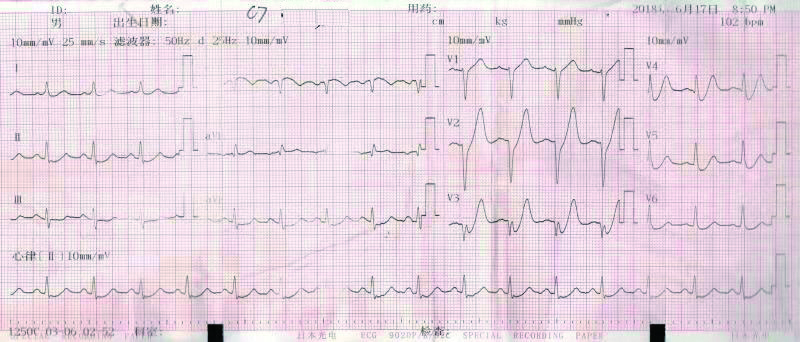

2 结果 本研究收集7例De winter综合征患者,6例进行了急诊冠脉造影,胸痛至球囊扩张平均时间为3.3 h,1例进行择期冠脉造影。其中,3例为前降支近段严重病变,1例为第一对角支闭塞,3例为前降支中段闭塞,2例合并多支血管病变,5例为单支血管病变,均行前降支支架植入术(表 4)。1周内行心脏彩超检查,4例出现室壁运动减弱,2例EF值小于50%,2例心脏形态结构未见异常,1例患者术后第2天因个人原因自动出院,未完善心脏彩超(表 5)。观察7例患者住院期间心电图演变情况,其中有3例在PCI术后出现前壁导联ST段抬高,4例未出现ST段抬高(表 5)。病例1住院期间出现室性心动过速,病例7患在急诊科就诊时发生呼吸心搏骤停,经抢救后送导管室行急诊冠脉造影。另外,所有患者经药物及介入治疗后,均症状缓解出院,院外长期服用阿司匹林100 mg/d+替格瑞洛90 mg/12 h+阿托伐他汀40 mg/瑞舒伐他汀20 mg等药物,出院1个月后电话随访,7例患者均无胸痛、气促发作及再住院,无死亡病例。

表 5 7例患者的心电图演变及心脏彩超结果

| 编号 |

心电图是否演变为ST段抬高 |

心脏彩超 |

| 病例1 |

是(图 3~5) |

左心扩大,左室前间壁、前侧壁及心尖部运动减弱,EF 35% |

3 讨论 De winter综合征是近10年来新发现的心电图诊断,其诊断标准为:⑴胸前导联T波高尖对称; ⑵胸前V1-6导联J点压低1~3 mm,ST段呈上斜型下移; ⑶QRS波群通常不增宽或轻度增宽; ⑷可出现胸前导联R波递增不良; 大多数患者aVR导联ST段抬高1~2 mm。当然,这仅是心电图诊断,具体还要结合临床及其他辅助检查。目前其已被证实与前降支急性闭塞有关,占急性前壁心肌梗死的2%。虽然De winter综合征不属于STEMI范畴,但因其心血管事件的发生风险较高,有学者提出,其治疗时机应参照STEMI,尽早行冠脉造影及干预靶血管,改善预后。本文7例De winter综合征病例中,6例患者行急诊冠脉造影+PCI术,术后心脏彩超证实4例患者心功能恢复良好,1例(病例1)心脏收缩功能受到影响(EF 35%),恰巧该患者PCI术后心电图也演变为STEMI,是否演变为STEMI的De winter综合征患者的心功能较未演变为STEMI的患者更容易受损,有待于进一步证实。1例(病例5)择期冠脉造影+PCI术患者心功能明显受损,这可能与缺血时间长,心肌细胞损伤严重有关。另外,住院期间心血管事件发生、30 d再住院、死亡等方面,7例患者预后均良好。

De winter综合征的主要心电图改变为:胸前V1-V6导联ST段呈上斜型下移,T波对称高尖,多数患者aVR导联ST段轻度上抬。出现这种心电图改变的原因尚未清楚。传统观点认为ST段压低,是因为心肌细胞受损后,由于不能正常除、复极,导致正常与异常心肌细胞之间产生电位差,出现损伤电流,导致ST段出现了相对或直接偏移。近年来,有人提出离子流学说,正常时Ito电流分布为外膜>内膜,当心内膜心肌缺血时,内膜Ito电流明显增大,达到钙失活电位后,造成二相平台丢失,内外膜之间形成的电位差由高到低指向心内膜,背离探查电极,从而引起ST段压低[5]。刘元生[6]则认为,前壁导联ST段未抬高,可能与细胞膜上ATP敏感性钾通道(KATP)不能激活有关,其机制是心肌缺血使ATP产生缺乏。也有学者推测可能是反复心肌缺血,及各冠脉之间已形成广泛的侧支循环所致[7]。

De winter综合征表现为T波高尖,临床上应注意与急性心肌梗死超急性期、高钾等疾病相鉴别。有学者认为,De winter综合征不会演变成STEMI,与STEMI超急性期的鉴别关键在于密切监测心电图,如果是De winter综合征,其ST段不会抬高,而急性心肌梗死超急性期心电图会有动态演变,T波高尖之后会逐渐出现ST段抬高,R波下降甚至丢失,病理性Q波形成等特点,但这种观点与本研究观察到的情况不符,本文中病例1、病例5和病例6都观察到心电图演变为STEMI。临床上观察不到的原因可能是:⑴患者发病时间短,心电图还来不及演变为ST段抬高,就已行冠脉造影及支架植入开通血管。⑵ST段抬高可能是一过性的,开通血管后ST段又回落至基线。只有密切监测心电图,才可能真正发现问题。至于与高钾导致的T波高尖的鉴别,急查血清钾即可明确。De winter等[1]发现心电图表现为ST段上斜型压低,T波高尖的患者,冠脉造影均提示前降支近段闭塞,且为单支血管病变。本文中观察到,3例为前降支近段严重病变,1例为第一对角支闭塞,3例为前降支中段闭塞,2例合并多支血管病变,5例为单支血管病变。亦有研究发现,心电图表现为De winter综合征,但冠脉造影却提示左主干闭塞[8]。可见,本文的发现及Murat等[8]的发现提示De winter综合征的靶病变不一定局限于LAD近段。另外,从本文观察到的情况,患者发病年龄都相对年轻,且均为男性,2例合并高脂血症,与以往文献报道[9]相符。